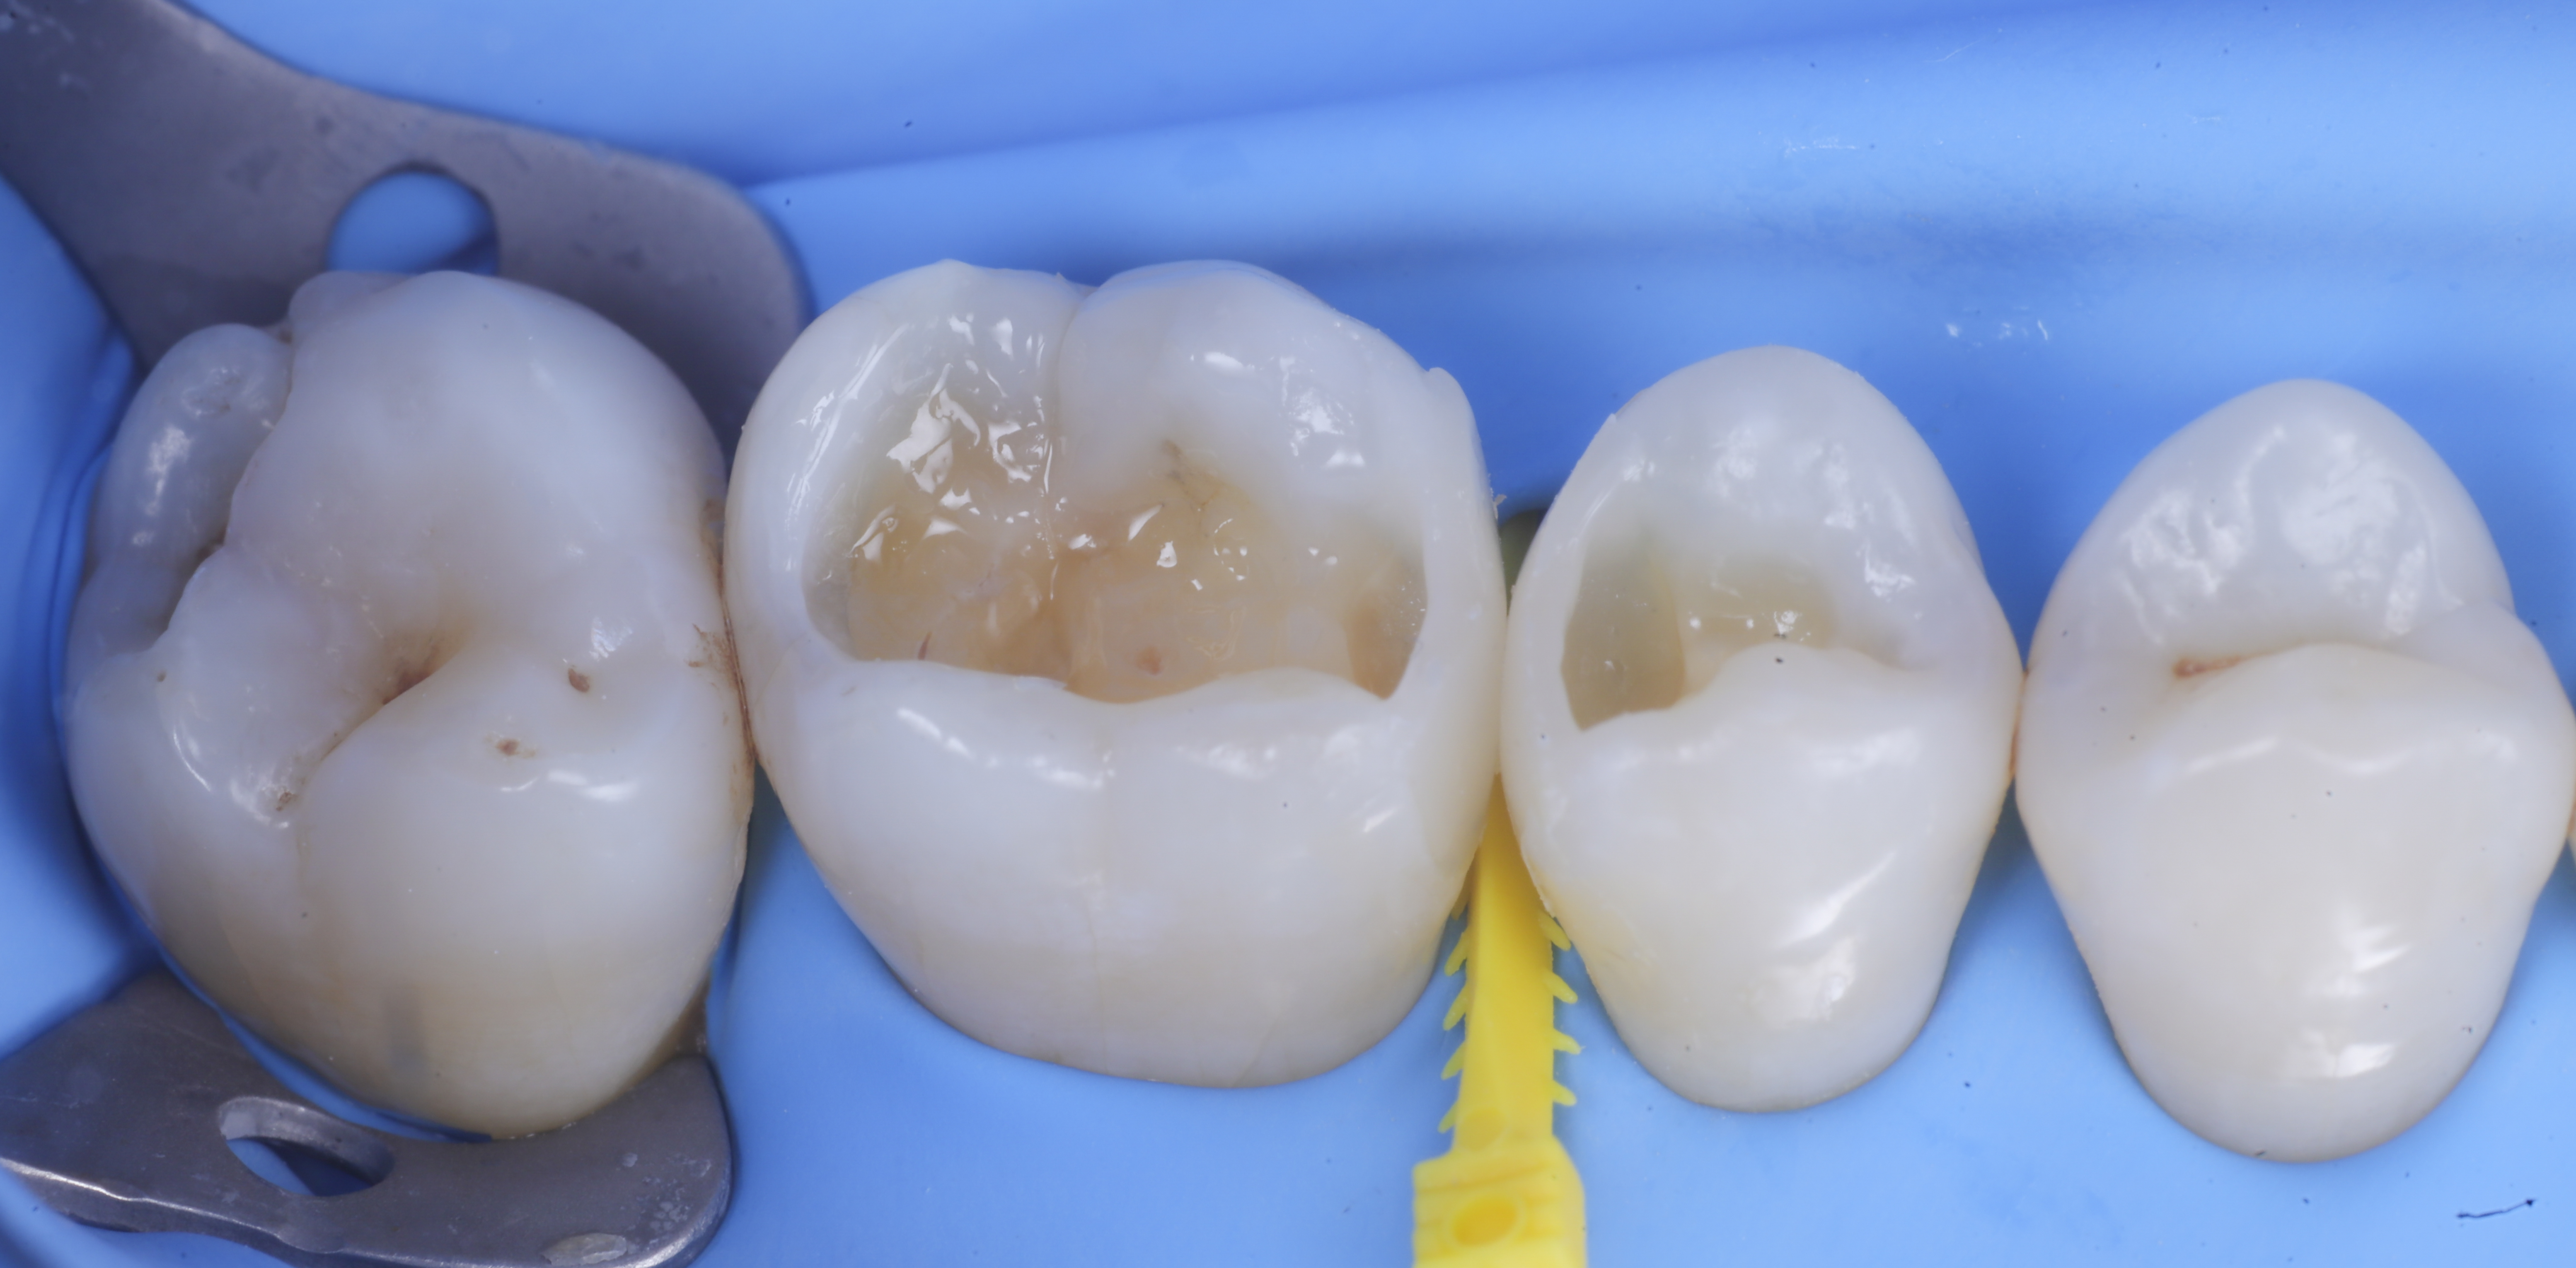

Modellazione delle pareti inter-prossimali

A questo punto si procede con la stratificazione e modellazione di una delle due pareti inter-prossimali e si polimerizza. Si elimina quindi la matrice della parete appena eseguita sposando l’anello che viene immediatamente rialloggiato.

Successivamente, eliminato lo spessore dato dalla seconda matrice, si procede con la creazione della seconda parete.

Trasformate le cavita da II classi a I classi si procede con la classica modellazione cuspide per cuspide, sfruttando le caratteristiche meccaniche e anche estetiche dei materiali compositi bulk.

foto 6 Aspetto occlusale delle pareti interprossimali appena create

foto 7 Aspetto vestibolare delle pareti interprossimali appena create

foto 8 Modellazione ed aspetto occlusale